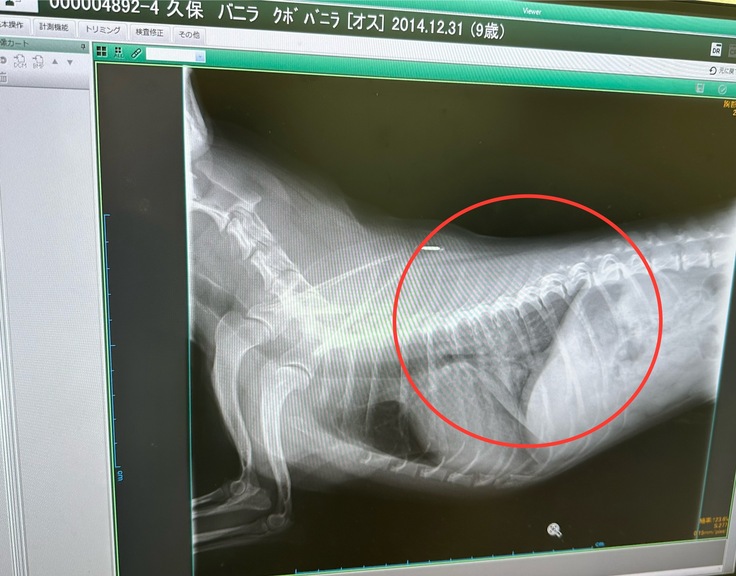

(入院中の肺水腫の画像。本来は黒色です)

心臓が収縮して血液を送り出すとき、僧房弁が完全に閉鎖せず、血液が逆流してしまう病気です。初期は無症状ですが進行すると肺水腫などの命に関わる状態(心不全)を発症することがあります。

肺水腫に罹患した後の生存期間中央値は9か月くらいだそうです。

我が家のバニラは肺水腫で入院中思うように薬が効いてくれず入院期間が延びていました。

若いのに心臓の状態がよくないと言われとても心配しました。